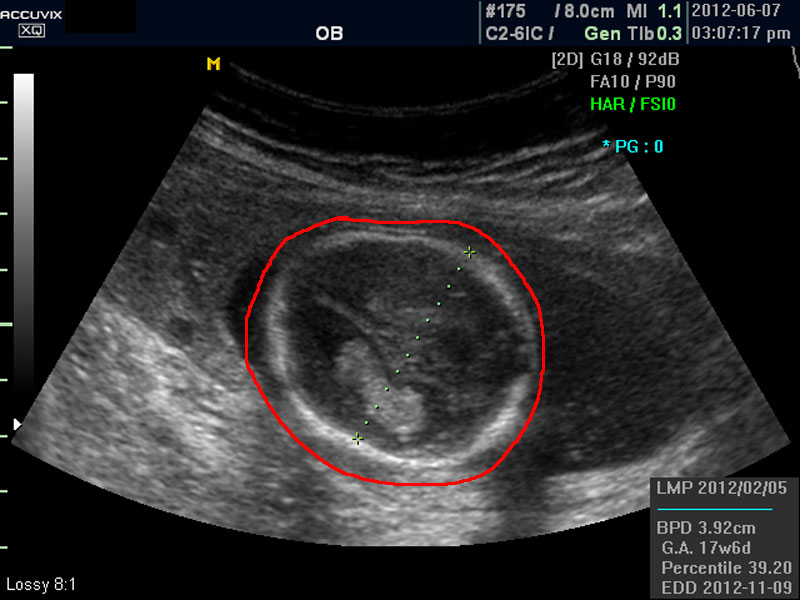

태아의 머리가 정상 모양인가 크기는 정상인가 하는 것을 살펴 본 후에는 태아의 크기를 측정하고 가슴, 복부, 엉덩이 부분, 상하지 부분이 정상인가 하는 것을 살펴 봅니다.

위 사진에서 빨간 동그라미로 표시한 부분이 태아의 머리를 위에서 내려다 본 수평 단면입니다.

하얗게 보이는 것은 뼈이고 내부에 검게 보이는 것은 뇌실에 고인 척수액 부분이며 내부의 하얀 부분은 뇌조직과 뇌실 내 맥락막이라고 하는 것입니다.

4. BPD

Biparietal Diameter의 약자로 머리를 위에서 보아서 양쪽 옆통수에서 반대쪽 옆통수까지의 길이입니다.

이는 임신 중기부터 후기까지 태아의 발육을 판단하는 중요한 지표이며 태아의 체중을 예측하는 데 쓰이는 지표 중 하나입니다.

3. GA

Gestational Age의 약자로 우리말로는 임신 주기라고 하며 CRL이나 BPD등을 기준으로 했을때 임신 몇주 며칠에 해당하는 지 나타낸 것입니다.

5.EDD

Estimated Due Date의 약자로 초음파 측정치를 바탕으로 산출한 출산 예정일입니다.